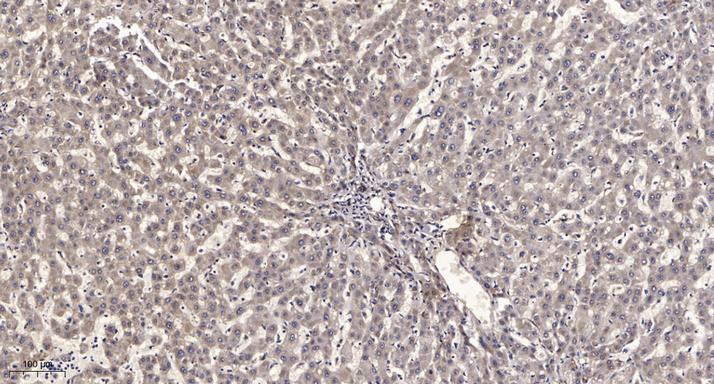

Dilution:WB 1:500-2000;IHC 1:50-300

Expression:Widely expressed. Expressed at high levels in the liver, adipose tissue, skeletal muscle and brain. Also expressed in endothelial cells (ECs), vascular smooth muscle cells (VSMCs) and macrophages. Expression oscillates diurnally in the suprachiasmatic nucleus (SCN) of the hypothalamus as well as in peripheral tissues. Expression increases during the differentiation of pre-adipocytes into mature adipocytes. Expressed at high levels in some squamous carcinoma cell lines.